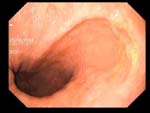

Рефлюкс-эзофагит Рефлюкс-эзофагит

Рефлюкс-эзофагит

Пациент С., 65 лет.

Рефлюкс - эзофагит II ст., дуодено-гастро-эзофагальный рефлюкс, ахалазия пищевода.

Институт терапии имени Л.Т. Малой АМН Украины,

отделение гастроэнтерологии, врач В. Жукова

Протокол.

Эндоскоп GIF - V70 во время акта глотания свободно введен в пищевод. Пищевод свободно проходим. Z-линия - 36-37 см от резцов. Складки продольные, просматриваются на всем протяжении. В н/3 пищевода (верхняя граница - 30-31 см от резцов) - 5 линейных эрозий с тенденцией к слиянию, покрыты фибрином, биопсия. При рвотных движениях отмечается поступление содержимого желудка (мутного, с примесью желчи) в пищевод. Розетка кардии зияет.